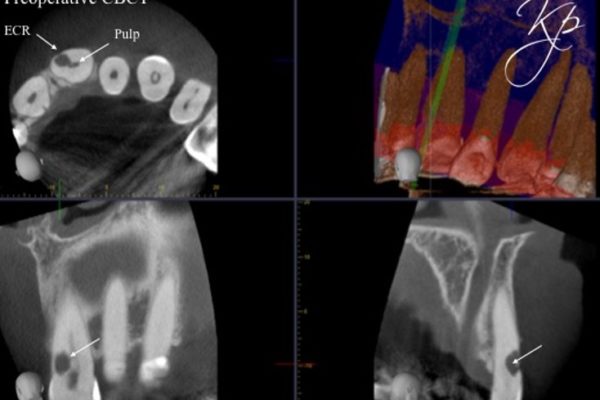

In my opinion CBCT is essential to assess external cervical resorption lesions prior to treatment.

I carried out a clinical study (Patel et al, 2016), which showed periapical radiographs significantly underestimated the size of lesions. They also provide limited information about the location and circumferential spread.

In addition to this, not all external cervical resorption lesions follow the ‘typical’ radiographic appearance mentioned above (Figure 5). A CBCT provides crucial information to obtain successful outcome.

Figure 5: From the PA radiograph LR5 has the classical appearance of internal resorption.

However, the CBCT scan shows the resorption is external cervical resorption.

The resorption starts buccally at the cervical margin. It extends down the root and spreads 360º around the root canal.

We often see this appearance because the canal is surrounded by a protective predentine layer, which is more resistant to resorption